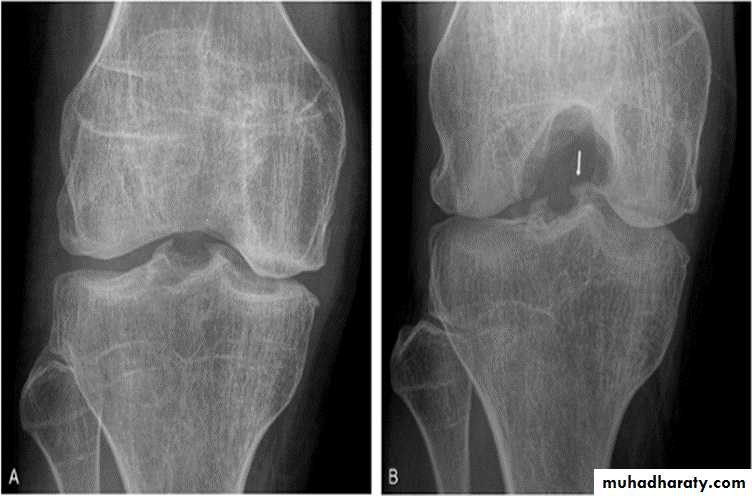

lumbar vertebral bodies (advanced case).Osteochondritis dissecans

affects the large articular surface , commomnly medial femural condylee ,talus and trochlea .Ends by separation of the affected part in to the joint space resulting in intra-articular loose body .

Osteochondritis dissecans of the medial femoral condyle Osteochondritis dissecans of the medial part of the articular surface